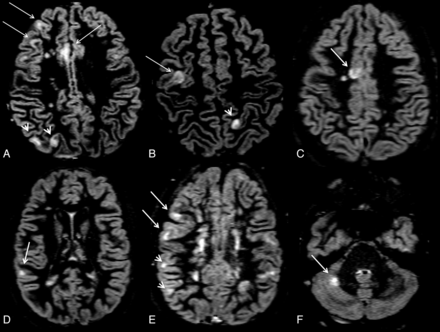

All images were assessed by consensus by 2 experienced observers (M.C. and D.S.), who were blinded to patient identity. At T0, the number of CLs was assessed on double inversion recovery images following the recent recommendations for CL scoring in patients with MS,18 with a count and classification interobserver variability of 2%. The lesions were recognized for their high signal intensity and were distinguishable as lesions confined within the cortical ribbon and not involving the underlying subcortical white matter (Fig 1A-F). At T0, the number of contrast-enhancing lesions was also scored, whereas at T1, T2, and T3, only the number of new CLs and new T2 WM lesions were evaluated.

Axial double inversion recovery images at study entry from a 14-year-old adolescent male with relapsing-remitting multiple sclerosis. The EDSS score at study entry was 2.5. Arrows identify pure intracortical lesions, whereas arrowheads identify mixed WM/GM lesions.

No difference in the morphology of CLs was observed in patients with cMS compared with those with aMS (Fig 1); however, the number of patients with CLs was higher in those with aMS than in patients with cMS (P < .001); patients with aMS also showed higher CL volume (P < .001), CL number (P < .001), and T2WMLV (P < .001) than patients with cMS, while the number of patients with contrast-enhancing lesion and the contrast-enhancing lesion number did not differ (P = .56 and P = .41) between the 2 groups (Table 1).